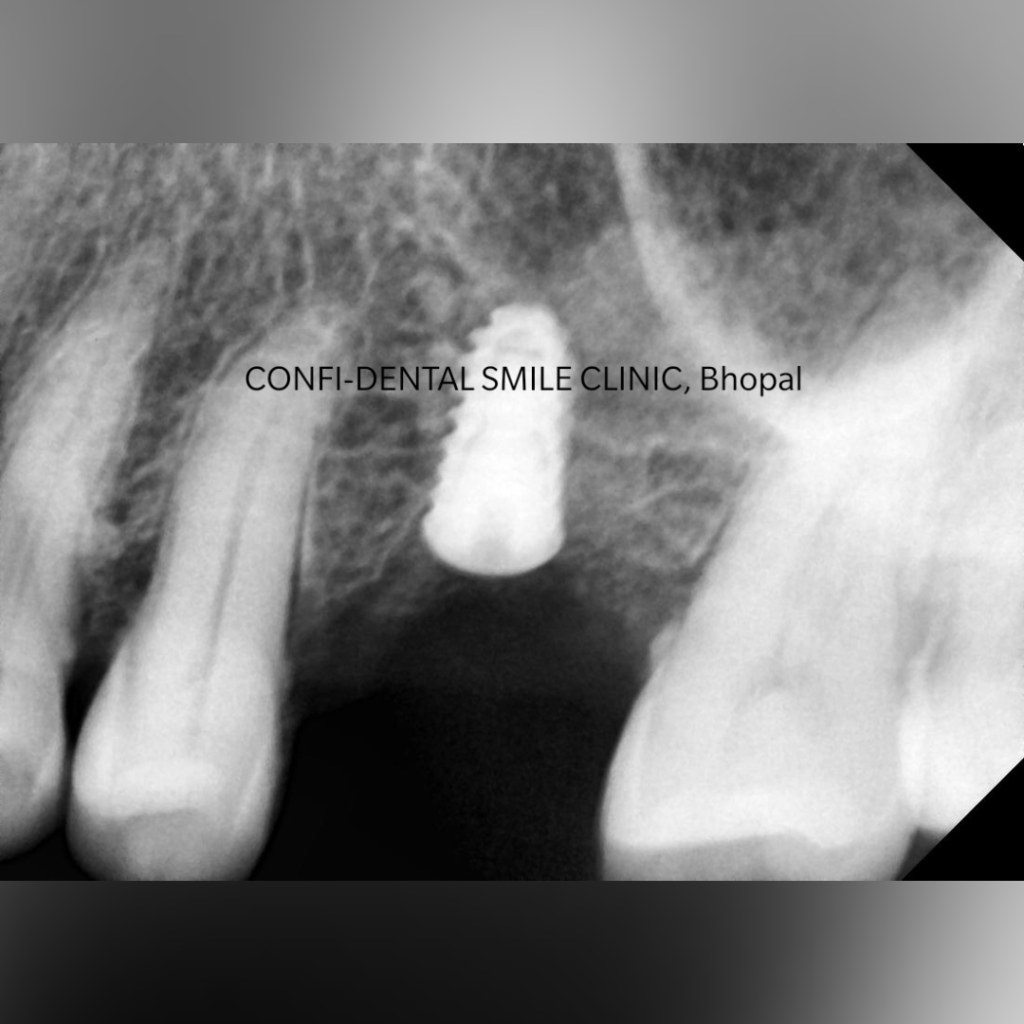

Step 1: Consultation and Examination

The first step involves a detailed dental examination, which may include:

- Clinical evaluation

- Digital scanning

- X-rays or CBCT imaging

This helps determine whether the patient is a suitable candidate for dental implants.

Using digital scans and imaging, the dentist carefully plans the position of the implant to ensure optimal stability and aesthetics.

Step 3: Implant Placement

During this stage, the titanium implant is placed into the jawbone under local anesthesia. The procedure is generally comfortable and minimally invasive.